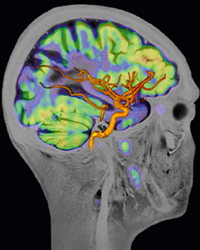

■参考:「Biograph mMR」で撮影された画像

2. 脳血管の血流状態と腫瘍の活動性が同時収集でき,より正確な評価が可能

さらに脳機能研究への応用にも期待が高まっている。機能的MRI(functional MRI),およびPETは,ともに脳機能解析へ重要な役割を果たしているが,この二つのデータを同時収集した研究評価は現在のところ特殊な実験装置による動物実験に限られている。今後「Biograph mMR」が脳機能研究における新たな診断ツールになると期待されている。同様に脳神経疾患においても,PET代謝情報に加え,MRIの豊富な画像コントラストや血流(MRアンギオグラフィ),神経線維走行(トラクトグラフィ)を一度の検査で実施でき,形態情報,物理的情報,生化学的情報が総合的に得られ,包括的な診断情報を,短時間の検査ワークフローで得ることができる。